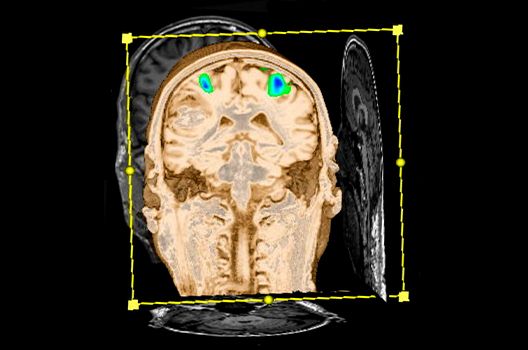

In der Neuroradiologie sind wir häufig mit Fragestellungen konfrontiert, die mehrere Fachgebiete oder auch Methoden betreffen. So arbeiten wir auch in der Forschung intensiv mit anderen Abteilungen des Universitätsklinikums zusammen, um Prozesse und Techniken bei der Diagnostik und Therapie neurovaskulärer Erkrankungen und vaskulärer Anomalien zu optimieren.

Zudem ist das Universitätsklinikum Tübingen das erste Zentrum Europas mit einem deckenmontierten intraoperativen Hochfeld-Magnetresonanztomographen, mit dem bereits während einer Hirnoperation MRT-Bilder angefertigt und ausgewertet werden können. In enger Kooperation mit der hiesigen Neurochirurgie können wir somit zu nahezu jedem Zeitpunkt der OP die genaue Lagebeziehung zu wichtigen anatomischen Strukturen darstellen und das Resektionsausmaß überprüfen.